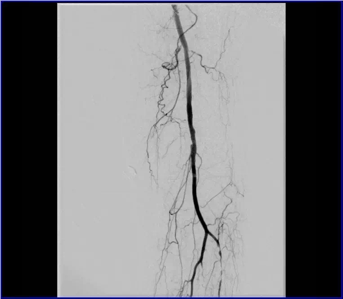

股動(dòng)脈閉塞

動(dòng)脈閉塞處支架植入